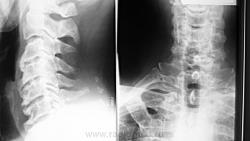

Соглашусь с коллегой Nela! Дегенеративные изменения шейного отдела позвоночника. Обызвествления передней продольной связки с образованием костных мостиков между телами позвонков. Деформирующий спондилез. Можно добавить остеохондроз(снижена высота дисков, склероз замыкательных пластин, артроз унко-вертебральных сочленений). Для Бехтерева - слишком зрелый возраст.

Диагноз основывается на данных рентгенографии позвоночника. Выявляется патогномоничный признак — оссификация передней продольной связки, первоначально в грудном отделе. В норме эта связка тонкая, при рентгенографии не видна, проходит вдоль всего позвоночника, огибает межпозвоночные диски и прикрепляется к телам позвонков; в результате оссификации эта связка становится рентгенопозитивной. Патологический процесс в связке обычно начинается в области тел позвонков, постепенно распространяется на другие отделы связки, что приводит к резкому и неравномерному ее утолщению (рис.), иногда до 10—20 мм. На рентгеновских снимках в прямой проекции в выраженных случаях позвоночник окружен по бокам лентовидными образованиями костной плотности с неровными контурами, как бы стекающими вдоль позвоночного столба, выгибаясь на уровне межпозвоночных дисков и соприкасаясь с телами позвонков. Позвоночник на определенных уровнях становится как бы закованным вновь образованной костной тканью (анкилозирующий гиперостоз позвоночника). Диагноз Ф. б. считается достоверным, если определяется непрерывное окостенение передней продольной связки на протяжении не менее четырех последовательных сегментов позвоночника вдоль переднелатеральной его части при условии отсутствия в этой области признаков остеохондроза, а также рентгенологических признаков сакроилеита. При рентгенографии различных отделов периферического скелета выявляются окостенение мест прикрепления сухожилий и связок к костям в виде шпор, бахромы, а иногда оссификация капсул суставов.

Анкилозирующийспондилоартрит(болезньБехтерева) можно включать в диф. ряд, только если видим анкилозирование межпозвонковых (межпозвоночных) суставов. В этом примере его нет!